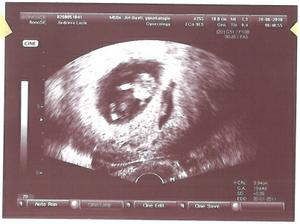

29. dubna 2010 odběr vajíček, 3.5. transfer 2 embryí, pozitivní test, UZ - jedno miminko, 2. UZ - dvojčátka